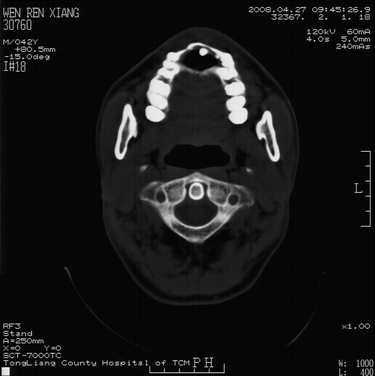

以下是引用随光逐影在2008-4-27 10:26:00的发言:[br]考虑为:上颌骨(中线区)含牙囊肿并向鼻腔穿破。

以下是引用前行在2008-4-27 11:30:00的发言:[br]含牙囊肿可能性大

以下是引用余辉在2008-4-27 16:43:00的发言:[br]考虑上颌骨正中囊肿,伴不全上颌骨正中裂,囊肿与鼻前庭有瘘道,所以表现为腔内炎性粘膜增厚而无囊液